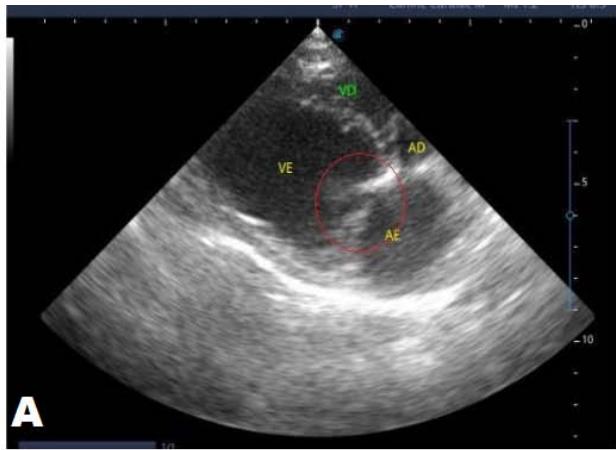

An echocardiogram (ECHO) (Figure 1) showed a thickened mitral valve and enlarged heart chambers. At first was prescribed Pimobendan PO at a dose of $0.25\mathrm{mg/kg}$ BID, continuous use, and requested to return in 30 days.

Figure 1: Echocardiogram 2021: Thickened/degenerated mitral valve (A); Observed in Doppler mode, significant mitral valve insufficiency (B); Hemodynamic assessment - Mitral regurgitation gradient: $3.45 \mathrm{~m} / \mathrm{s} / 47.68 \mathrm{mmHg}$; enlargement of left cardiac chambers; left ventricular diastolic dimension above normal limits was observed

In the reported, he was asymptomatic, and the echocardiographic examination showed enlargement of the left heart chambers, thickened and degenerated mitral valve (Figure 1), left ventricular diastolic dimension above normal limits. with normal systolic function parameters, characterizing systolic dysfunction. The thickening and degeneration of the mitral valve indicates its insufficiency, and the other changes represent diastolic dysfunction.